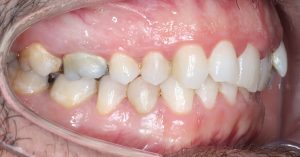

Maloclusión clase II

Se caracteriza por una relación anormal entre los dientes superiores e inferiores, donde los dientes superiores están demasiado adelantados en comparación con los inferiores.

Esto puede generar problemas funcionales, como dificultad para masticar, y también afectar la estética facial.

INTENSIVE

52 Semanas de tratamiento